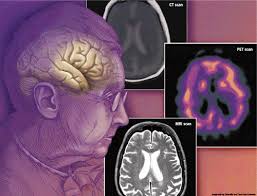

اختلال فراگیر رشد ، عبارتی است که در حال حاضر برای اشاره به مشکلات روان شناختی شدید که در طفولیت ظاهر میشود، بکار میرود. اختلالات فراگیر رشد ، در بردارنده آشفتگی شدید در رشد شناختی ، اجتماعی ، رفتاری و هیجانی کودک است که عوارض گستردهای بر روی فرایند رشد دارد. یکی از این اختلالات ، اوتیسم ، در قلمروهای پژوهشی و بالینی ، به وضوح برجسته شده است. اوتیسم ، کیفیات اصلی انسانی را متاثر میسازد، یعنی معاشرت بین فردی و رابطه پیچیده را مختل میسازد. کودکان مبتلا به اوتیسم ، تقایص شدید در روابط و تبدیل اجتماعی ، بازی بین فردی و ارتباط ظاهر میسازند